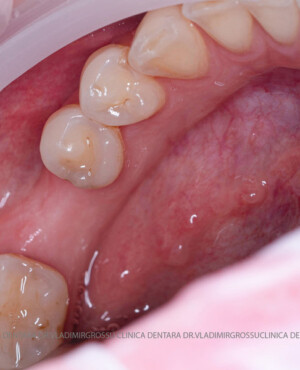

Aditia gingivală este o procedură chirurgicală ce corectează diverse probleme estetice și funcționale, cum ar fi recesiunea gingivală. În implantologia modernă, aditia de țesut moale este utilizată aproape în fiecare intervenție de inserție a implantului dentar pentru a asigura un aspect estetic natural și o bună integrare a implantului în cavitatea bucală.

Adiția osoasă are un rol crucial pentru poziționarea corectă și stabilă a implanturilor dentare. Clinica stomatologică Dr. Grossu din Chișinău promovează o abordare chirurgicală estetică și predictibilă, adaptată fiecărui caz în parte.

Procesul de refacere osoasă este complex, însă, simplificat, se bazează pe faptul că osul adăugat se integrează treptat, fiind înlocuit parțial cu os natural, oferind astfel suportul necesar implantului.